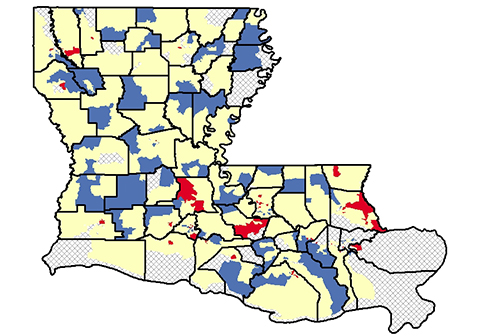

LSU Health New Orleans LA Tumor Registry Releases 6th Census Tract Cancer Incidence Report

LSU Health New Orleans Louisiana Tumor Registry (LTR) has published the sixth report of statewide cancer incidence rates by census tract. The publication, which reports 2010-2019 combined cancer incidence data, found that 81% of the census tracts in Louisiana met publication criteria for all cancers combined. More